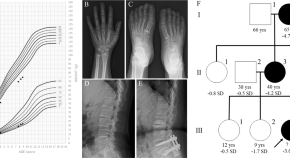

Andrea Superti-Furga, Ron Wevers, Clara van Karnebeek, Luisa Bonafé and colleagues identify mutations in NANS, which encodes the sialic acid synthase, in nine individuals with severe infantile-onset developmental delay and skeletal dysplasia. They describe abnormal metabolites accumulating because of deficient NANS enzyme activity and show that impaired sialic acid synthesis in zebrafish perturbs skeletal development, which can partially be rescued by supplementation with exogenous sialic acid.